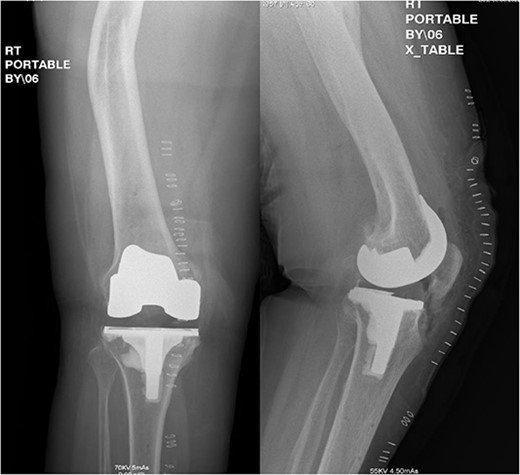

Spinal regional anesthesia was performed, and 1 g of cephazolin was administered, followed by prepping and draping of the right lower limb in the usual sterile manner. After inflation of an above-knee tourniquet, a right knee midline incision followed by a medial para-patellar arthrotomy was performed. Knee joint exposure with proximal medial tibia release was carried out, followed by application of check points plus two pins in each of the tibia and the femur (navigation receptors). The hip center of rotation was registered, followed by medial and lateral malleolus registration. All large femoral and tibial osteophytes were resected, followed by mapping of articular cartilage in the femur and tibia. After mapping and balancing extension and flexion gaps (Fig. 3), the following sizes were determined: four for the femur and three for the tibia. The distal femur cut was carried out at 90° to the mechanical axis with robotic assistance, utilizing a burr and the remaining femoral cuts were completed with a distal femoral jig and electrical saw. The tibia cut could be achieved with an extramedullary guide, but a burr was utilized for added accuracy regarding the tibial slope and angle of the cut. A trial was performed after completion of the femoral and tibial cuts; it showed good stability in both flexion and extension, with maintained patellar tracking. Copious irrigation with 3 L of normal saline and local anesthesia for the posterior capsule of the knee was performed, followed by cementation and final components placement. Then, the tourniquet was deflated and hemostasis was confirmed, followed by closure in layers and sterile dressing application. Postoperative radiographs showed good positioning of the components (Fig. 4).

Postoperative anteroposterior and lateral radiograph views of the status of post RATKA.